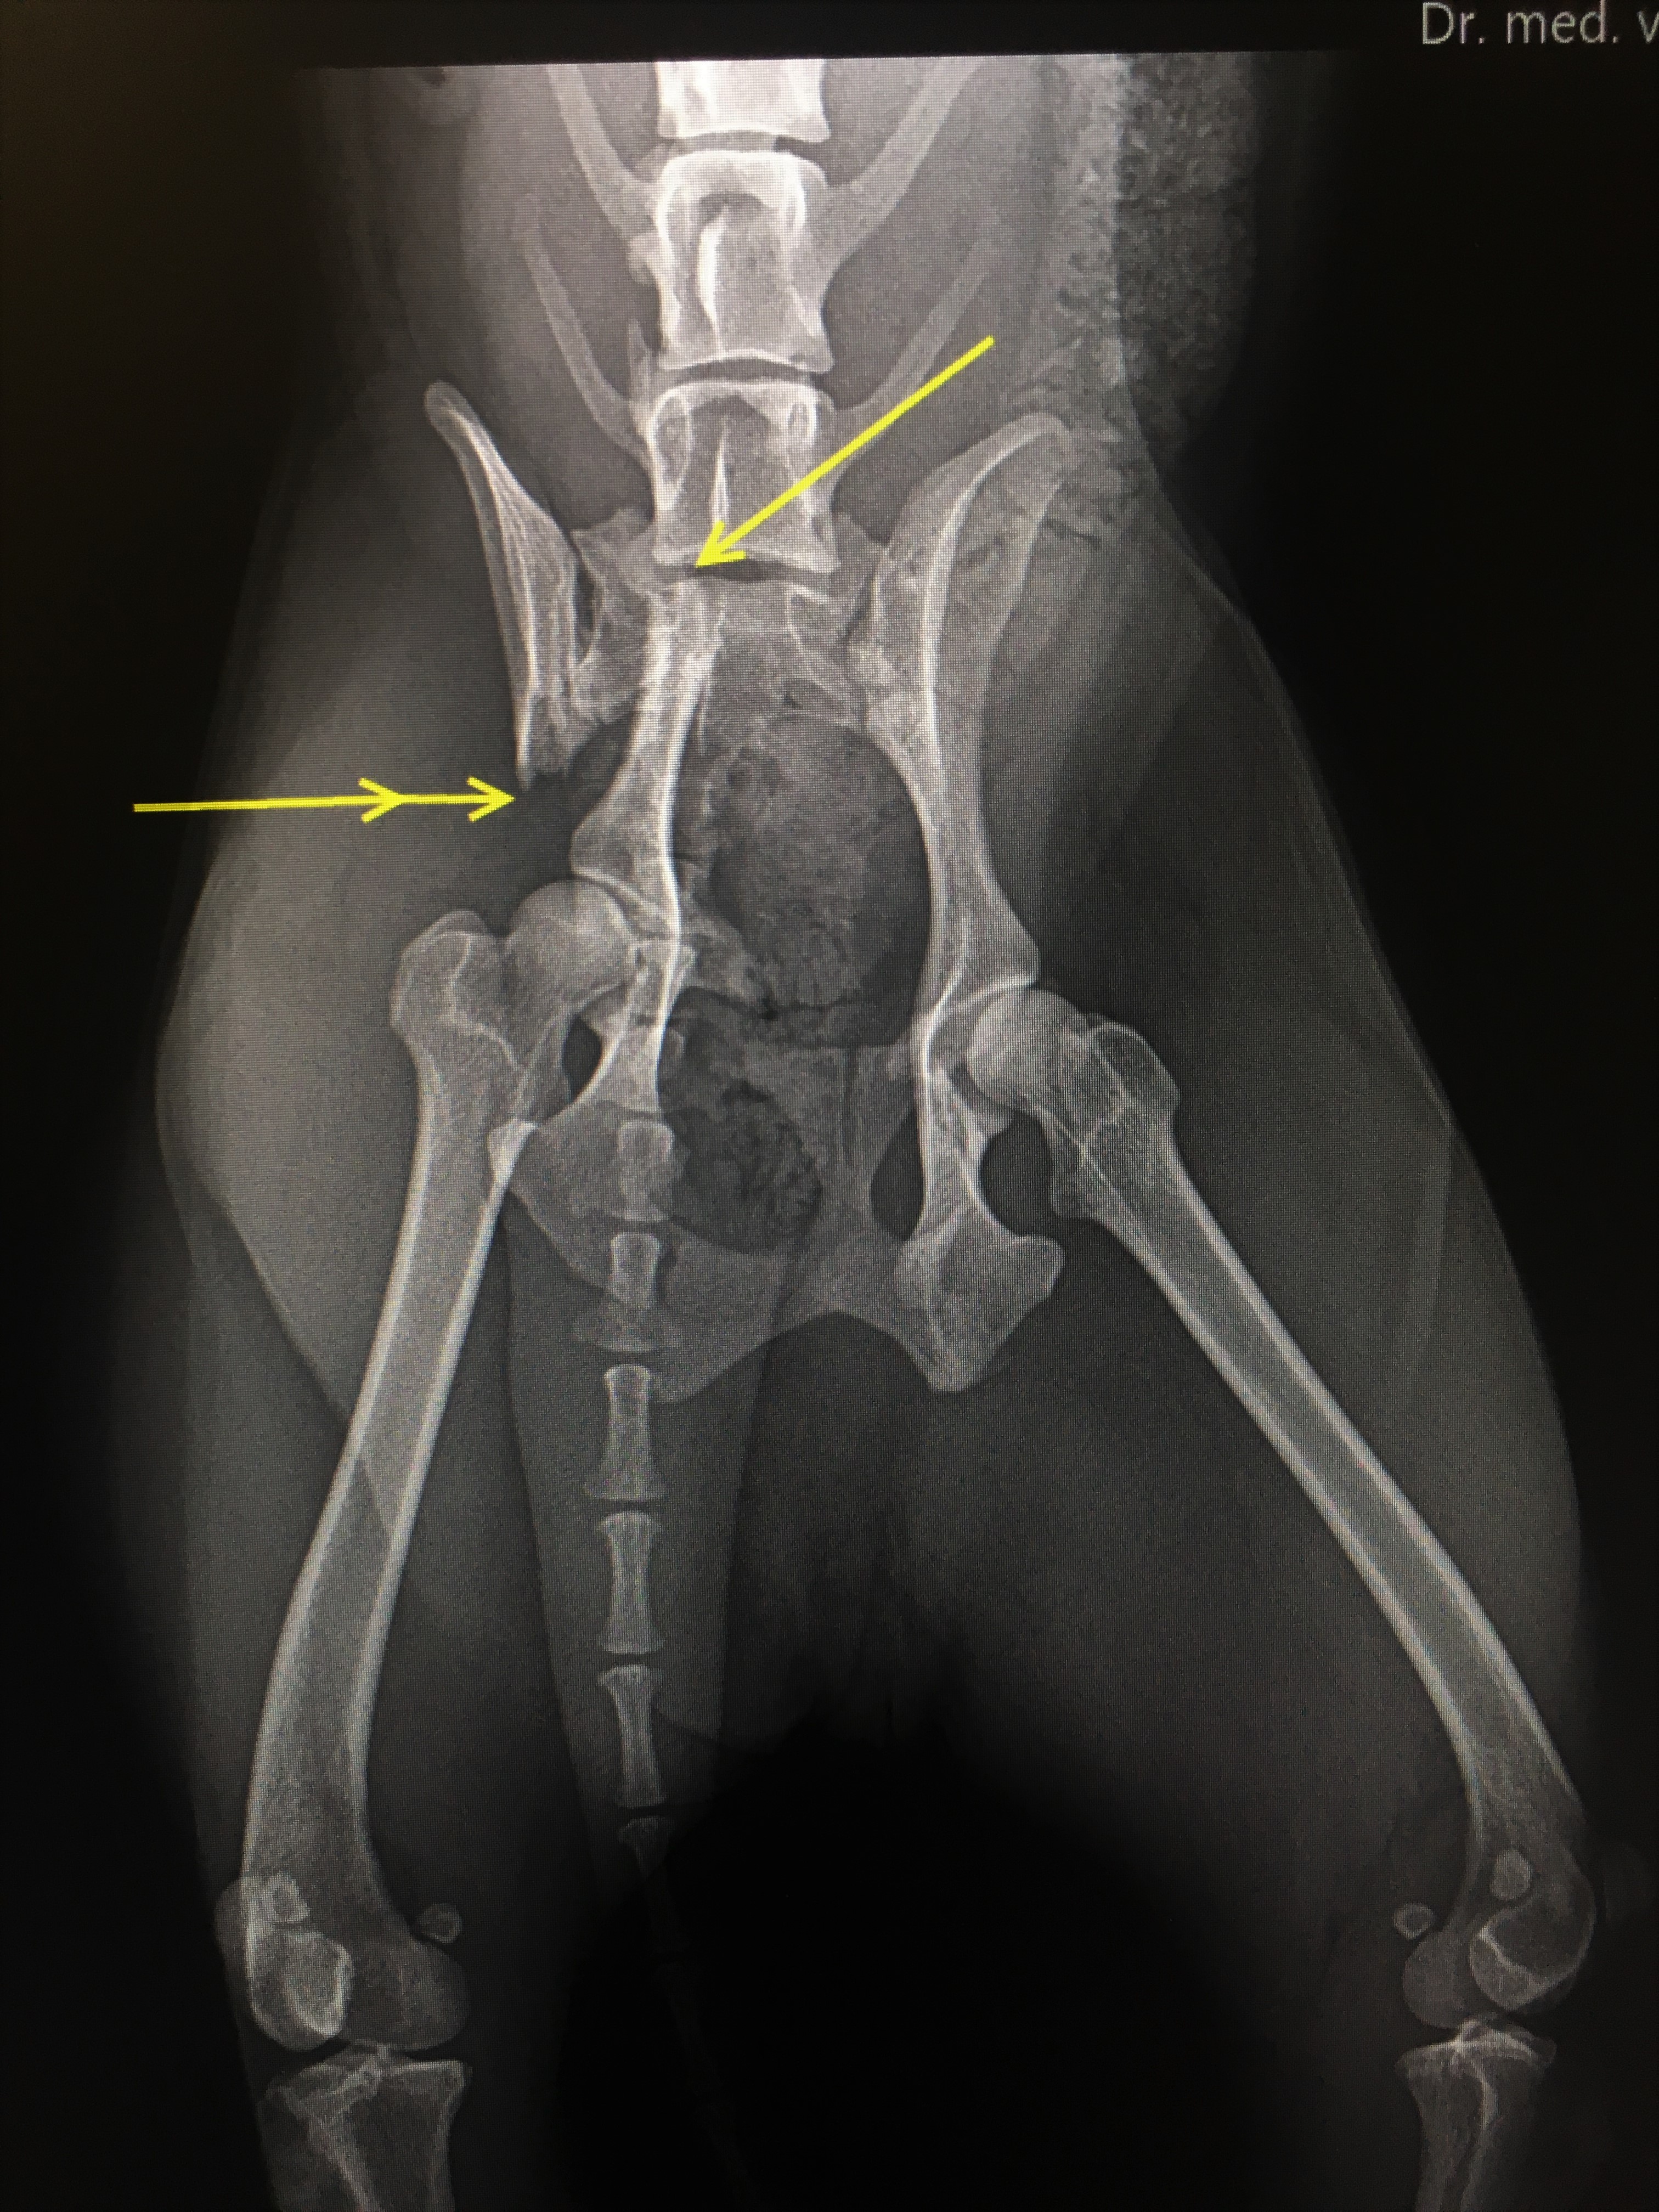

Beckenfraktur bei „Buntem Hund“ chirurgische durch

Der besondere Fall Leistenbruch mit Gebärmutter